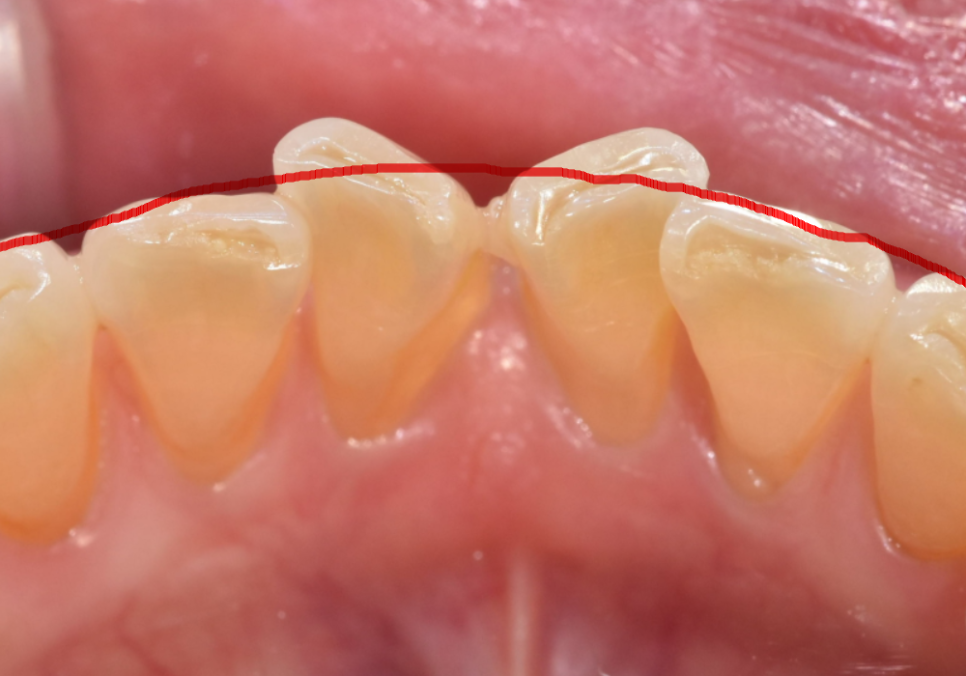

최근 아래 앞니가 나비 날개처럼 뻗어

고민이셨던 분이 찾아오셨습니다.

치아가 바깥으로 벌어져 있다 보니

평소 입술이 자꾸 걸리고

면 요리를 드실 때도 잘 끊기지 않아

무척 불편하셨다고 해요.

전체적인 치아 배열은 안정적이라,

앞니를 많이 깎아내지 않고도

충분히 배열을 맞출 수 있는 상태였습니다.

전체 치아를 이동시키는 교정 대신,

틀어진 각도만 정교하게

바로잡는 라미네이트로 가닥을 잡았고,